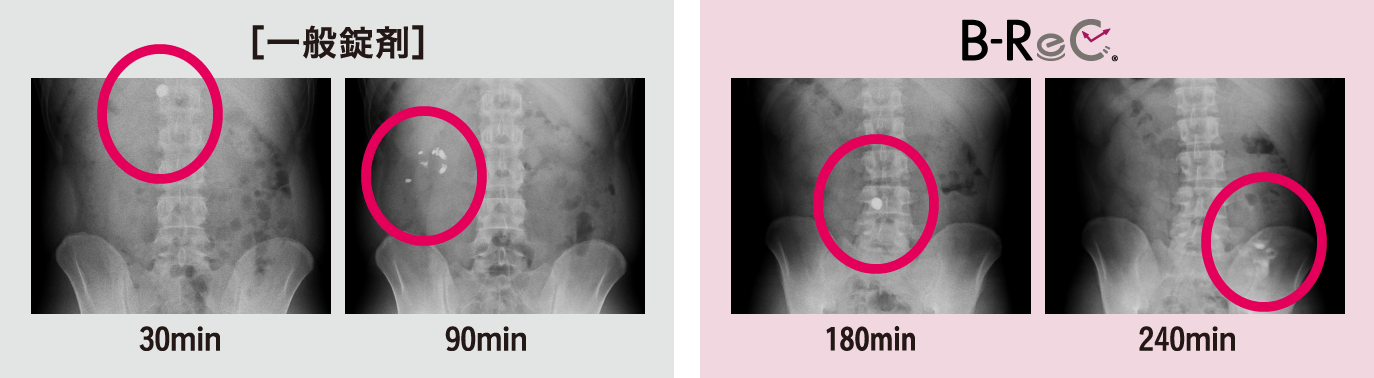

一般錠剤とB-ReC錠の体内動態を確認した。一般錠剤は90分以内に胃から十二指腸にかけて完全に崩壊したが、空腸崩壊型B-ReC錠では、摂取180分後の小腸上部(空腸)では崩壊せず240分後の小腸中部で崩壊した。

機能成分を消化管の目的部位に

デリバリーできる製剤であることが

証明された。 -